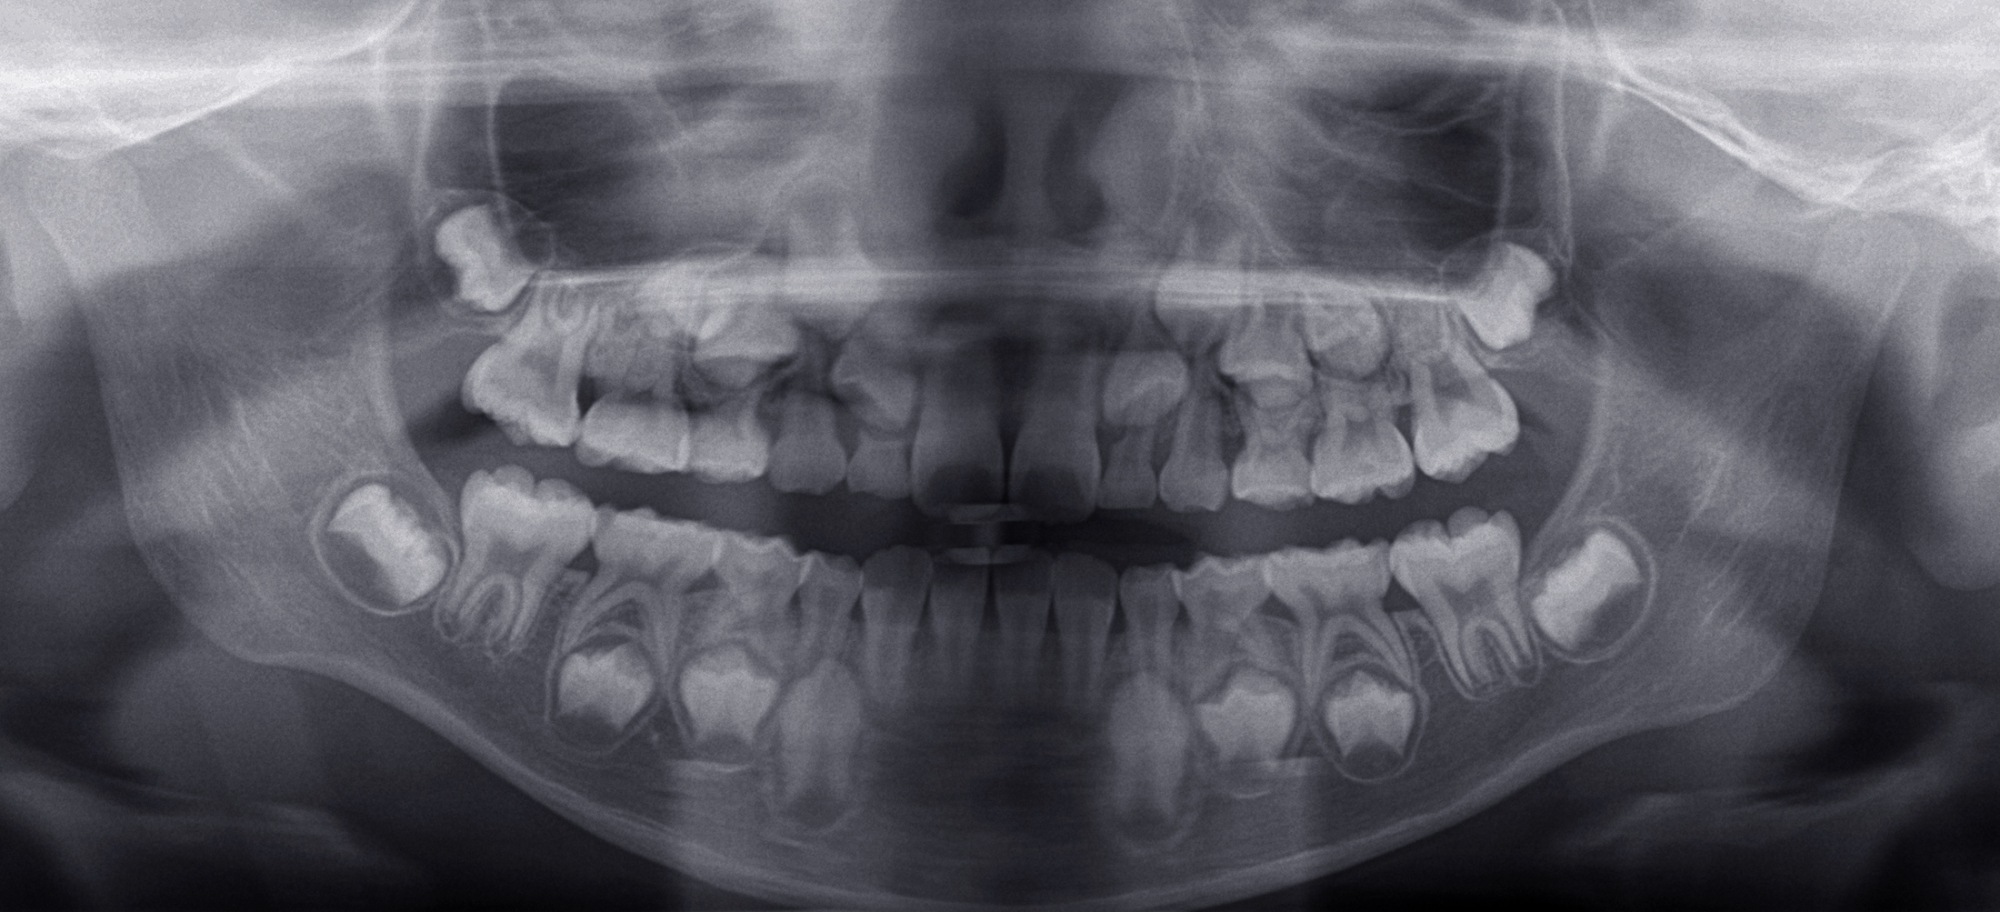

拡大床治療で顎のスペースを拡げられるのは11歳くらいまでです。そのため個人差はありますが遅くても小学校2年生までに始めなければなりません。下の前歯が生え替わりはじめた頃から下の前歯が4本、上の前歯が2本生え替わる頃までが始め時です。すでに上下4本とも生え替わってしまった場合にはすでに遅いことが多くあります。